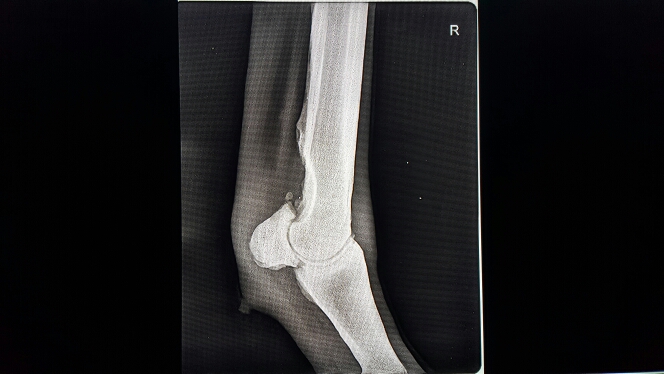

Помогите пожалуйста! Сделали рентгены, там в принципе и так видно что все плохо, но хотелось бы что бы кто-нибудь разъяснил что это и как можно помочь лошадке! Хотя бы снять боли! Так как вет внятно так и не объяснила что к чему. Заранее спасибо)

Нет, точного диагноза не поставили. Сказали только что кусочка кости не хватает, но это и так видно. Коваль наш сказал что скорее всего это сезамоидит.

Сесамоидит тоже, безусловно есть, но ИМХО он не главная проблема. Скорее всего проблема в кости, которая выше. Возможно там все еще идет лизис. Это весьма болезненный процесс.

Добавлю немного. Сесамовидная кость сильно деформирована. Не лечится. Еще мне кажется на снимке какие то мелкие обломки. Если это так, то они при движении травмируют ткани, а это больно. По идее можно устранить хирургически, но дорого и рискованно. Дырку в кости ну может быть где то за границей лечили бы операбельно, заполнив ее каким то составом. О подобных операциях я что то слышала, но в России таких вроде не делали и не делают. Учитывая жеребость, даже если у Вас есть огромные стредства на все смелые идеи и подобные эксперименты, год и даже больше ничего не сделать. К нагрузкам лошадь вряд ли сможет вернуться даже если найдутся супер опытные врачи.